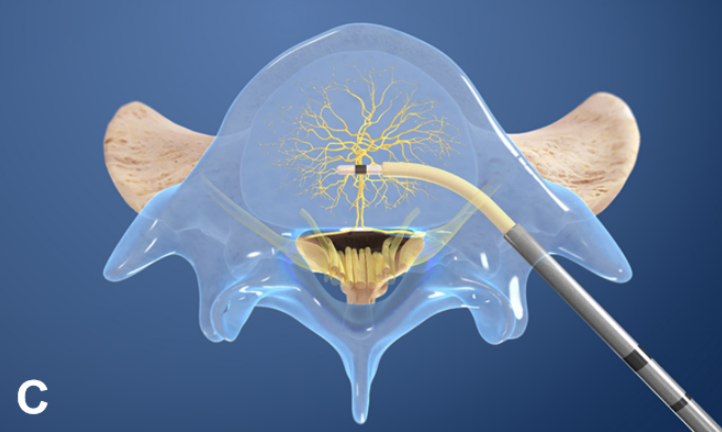

②椎体内椎基神经射频消融术

③经皮内镜下硬膜外椎基神经激光消融术

值得关注的是,系列前瞻性多中心随机对照研究和前瞻性观察研究证实椎体内椎基神经射频消融术可有效缓解疼痛性 Ⅰ 型或 Ⅱ 型 Modic 改变患者的腰痛症状,减少阿片类药物的用量,且疗效优于保守治疗。

国际脊柱外科手术学会指南也推荐采用椎体内椎基神经射频消融术治疗 Ⅰ 型或 Ⅱ 型 Modic 改变引起的慢性腰痛。

2021 年,Conger 等进行系统综述发现有中等质量的证据表明,在根据存在 Ⅰ 型或 Ⅱ 型 Modic 改变选择慢性腰痛患者时,椎体内椎基神经射频消融术可有效改善慢性腰痛患者的疼痛和功能障碍。这可能与灭活了椎体内的椎基神经, 阻断了神经传导通路有关。